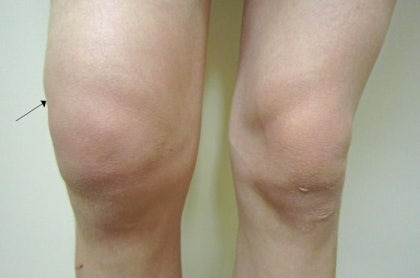

- 좌우 무릎 크기 차이

물이 더 차면 겉으로도 변화가 분명해집니다.

중기 증상의 특징

- 무릎이 눈에 띄게 부음

- 손으로 만지면 말랑하거나 팽팽한 느낌

- 열감 동반

- 압통 발생